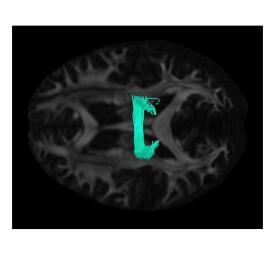

Figure 1 also compares the impact of varying the kernel bandwidth parameters for functional varifolds using similarity angle between pairs of these selected fibers (top right: CST (R), bottom left: CC, bottom right: IFOF (R)). We show variation over = 3, 5, 7, 9 and 11 (mm) and = 0.001, 0.005, 0.01, 0.05, and 0.1.

Comparing the parameter variation images in Figure 1 we observe that the cosine similarity values over the parameter space show similar trends for all pairs of fibers. This observation allows us to select a single pair of parameter values for our experiments. We have used = mm and = for our experiments based on the cosine similarity values in Figure 1. The smaller values for (mm) and (mm) will make the current fiber pairs orthogonal while for larger values we lose the discriminative power as all fiber pairs will have very high similarity.